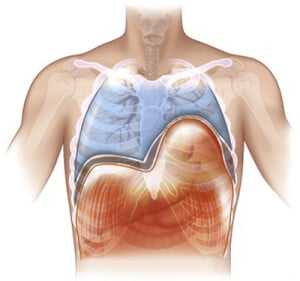

Диафрагма (diaphragma от греч. — перегородка), или грудобрюшная преграда — это куполообразная перегородка, которая разделяет грудную и брюшную полости. Выделяют центральную сухожильную и краевую мышечную части диафрагмы. Сокращаясь и расслабляясь диафрагма принимает участие в акте дыхания.

Диафрагма - сухожильно-мышечное образование, которое разделяет грудную и брюшную полости. Мышечная часть диафрагмы начинается по кругу нижней апертуры грудной клетки от грудины, внутренней поверхности хрящей VII-XII ребер и поясничных позвонков (грудинный, реберный и поясничный отделы диафрагмы). Мышечные волокна идут кверху и радиально и заканчиваются сухожильным центром, образовывая справа и слева куполообразные выпуклости. Между грудинным и реберным отделом есть грудинореберное пространство (треугольник Морганьи-Ларрея), заполненное клетчаткой. Поясничный и реберный отделы разделены пояснично-реберным пространством (треугольник Бохдалека). Поясничный отдел диафрагмы состоит с каждой стороны из трех ножек: внешней (латеральной), промежуточной и внутренней (медиальной). Сухожильные края обеих внутренних (медиальных) ножек диафрагмы образуют на уровне I поясничного позвонка левее от срединной линии дугу, которая ограничивает отверстие для аорты и грудного лимфатического протока. Пищеводное отверстие диафрагмы образовано в большинстве случаев за счет правой внутренней (медиальной) ножки диафрагмы, левая ножка принимает участие в его образовании лишь в 10% случаев. Через пищеводное отверстие диафрагмы проходят также - блуждающие нервы. Через межмышечные щели поясничного отдела диафрагмы проходят симпатические стволы, чревные нервы, непарная и полунепарная вены. Отверстие для нижней полой вены расположено в сухожильном центре диафрагмы.

Сверху диафрагма покрыта внутригрудной фасцией, плеврой и перикардом, снизу - внутрибрюшной фасцией и брюшиной. К забрюшинной части диафрагмы прилежать поджелудочная железа, двенадцатиперстная кишка, окруженные жировой капсулой почки и надпочечники. К правому куполу диафрагмы прилежит печень, к левому - селезенка, дно желудка, левая часть печени. Между этими органами и диафрагмой есть соответствующие связки. Правый купол диафрагмы расположен выше (четвертое межреберье), чем левый (пятое межреберье). Высота стояния диафрагмы зависит от конституции, возраста, наличия разных патологических процессов в грудной и брюшной полостях.

Выделяют статическую и динамическую функции диафрагмы. Статистическая функция диафрагмы заключается в поддержке разницы давления в грудной и брюшной полостях и нормальных взаимоотношений между их органами. Она зависит от тонуса диафрагмы. Динамическая функция диафрагмы обусловлена действием подвижной при дыхании диафрагмы на легкие, сердце и органы брюшной полости. Движения диафрагмы осуществляют вентиляцию легких, облегчают поступление венозной крови в правое предсердие, способствуют оттоку венозной крови от печени, селезенки и органов брюшной полости, движения газов в желудочно-кишечном тракте, акту дефекации, лимфообращения.